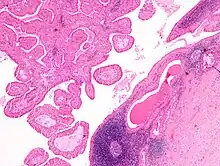

The appearance of this tumor under the microscope is unique. There are cystic spaces surrounded by two uniform rows of epithelial cells with centrally placed pyknotic nuclei. The cystic spaces have epithelium referred to as papillary infoldings that protrude into them. Additionally, the epithelium has lymphoid stroma with germinal center formation.

Intermediate magnification micrograph of a Warthin tumor.

Intermediate magnification micrograph of a Warthin tumor. -

High magnification micrograph of a Warthin tumor showing the characteristic bilayered epithelium.

High magnification micrograph of a Warthin tumor showing the characteristic bilayered epithelium.